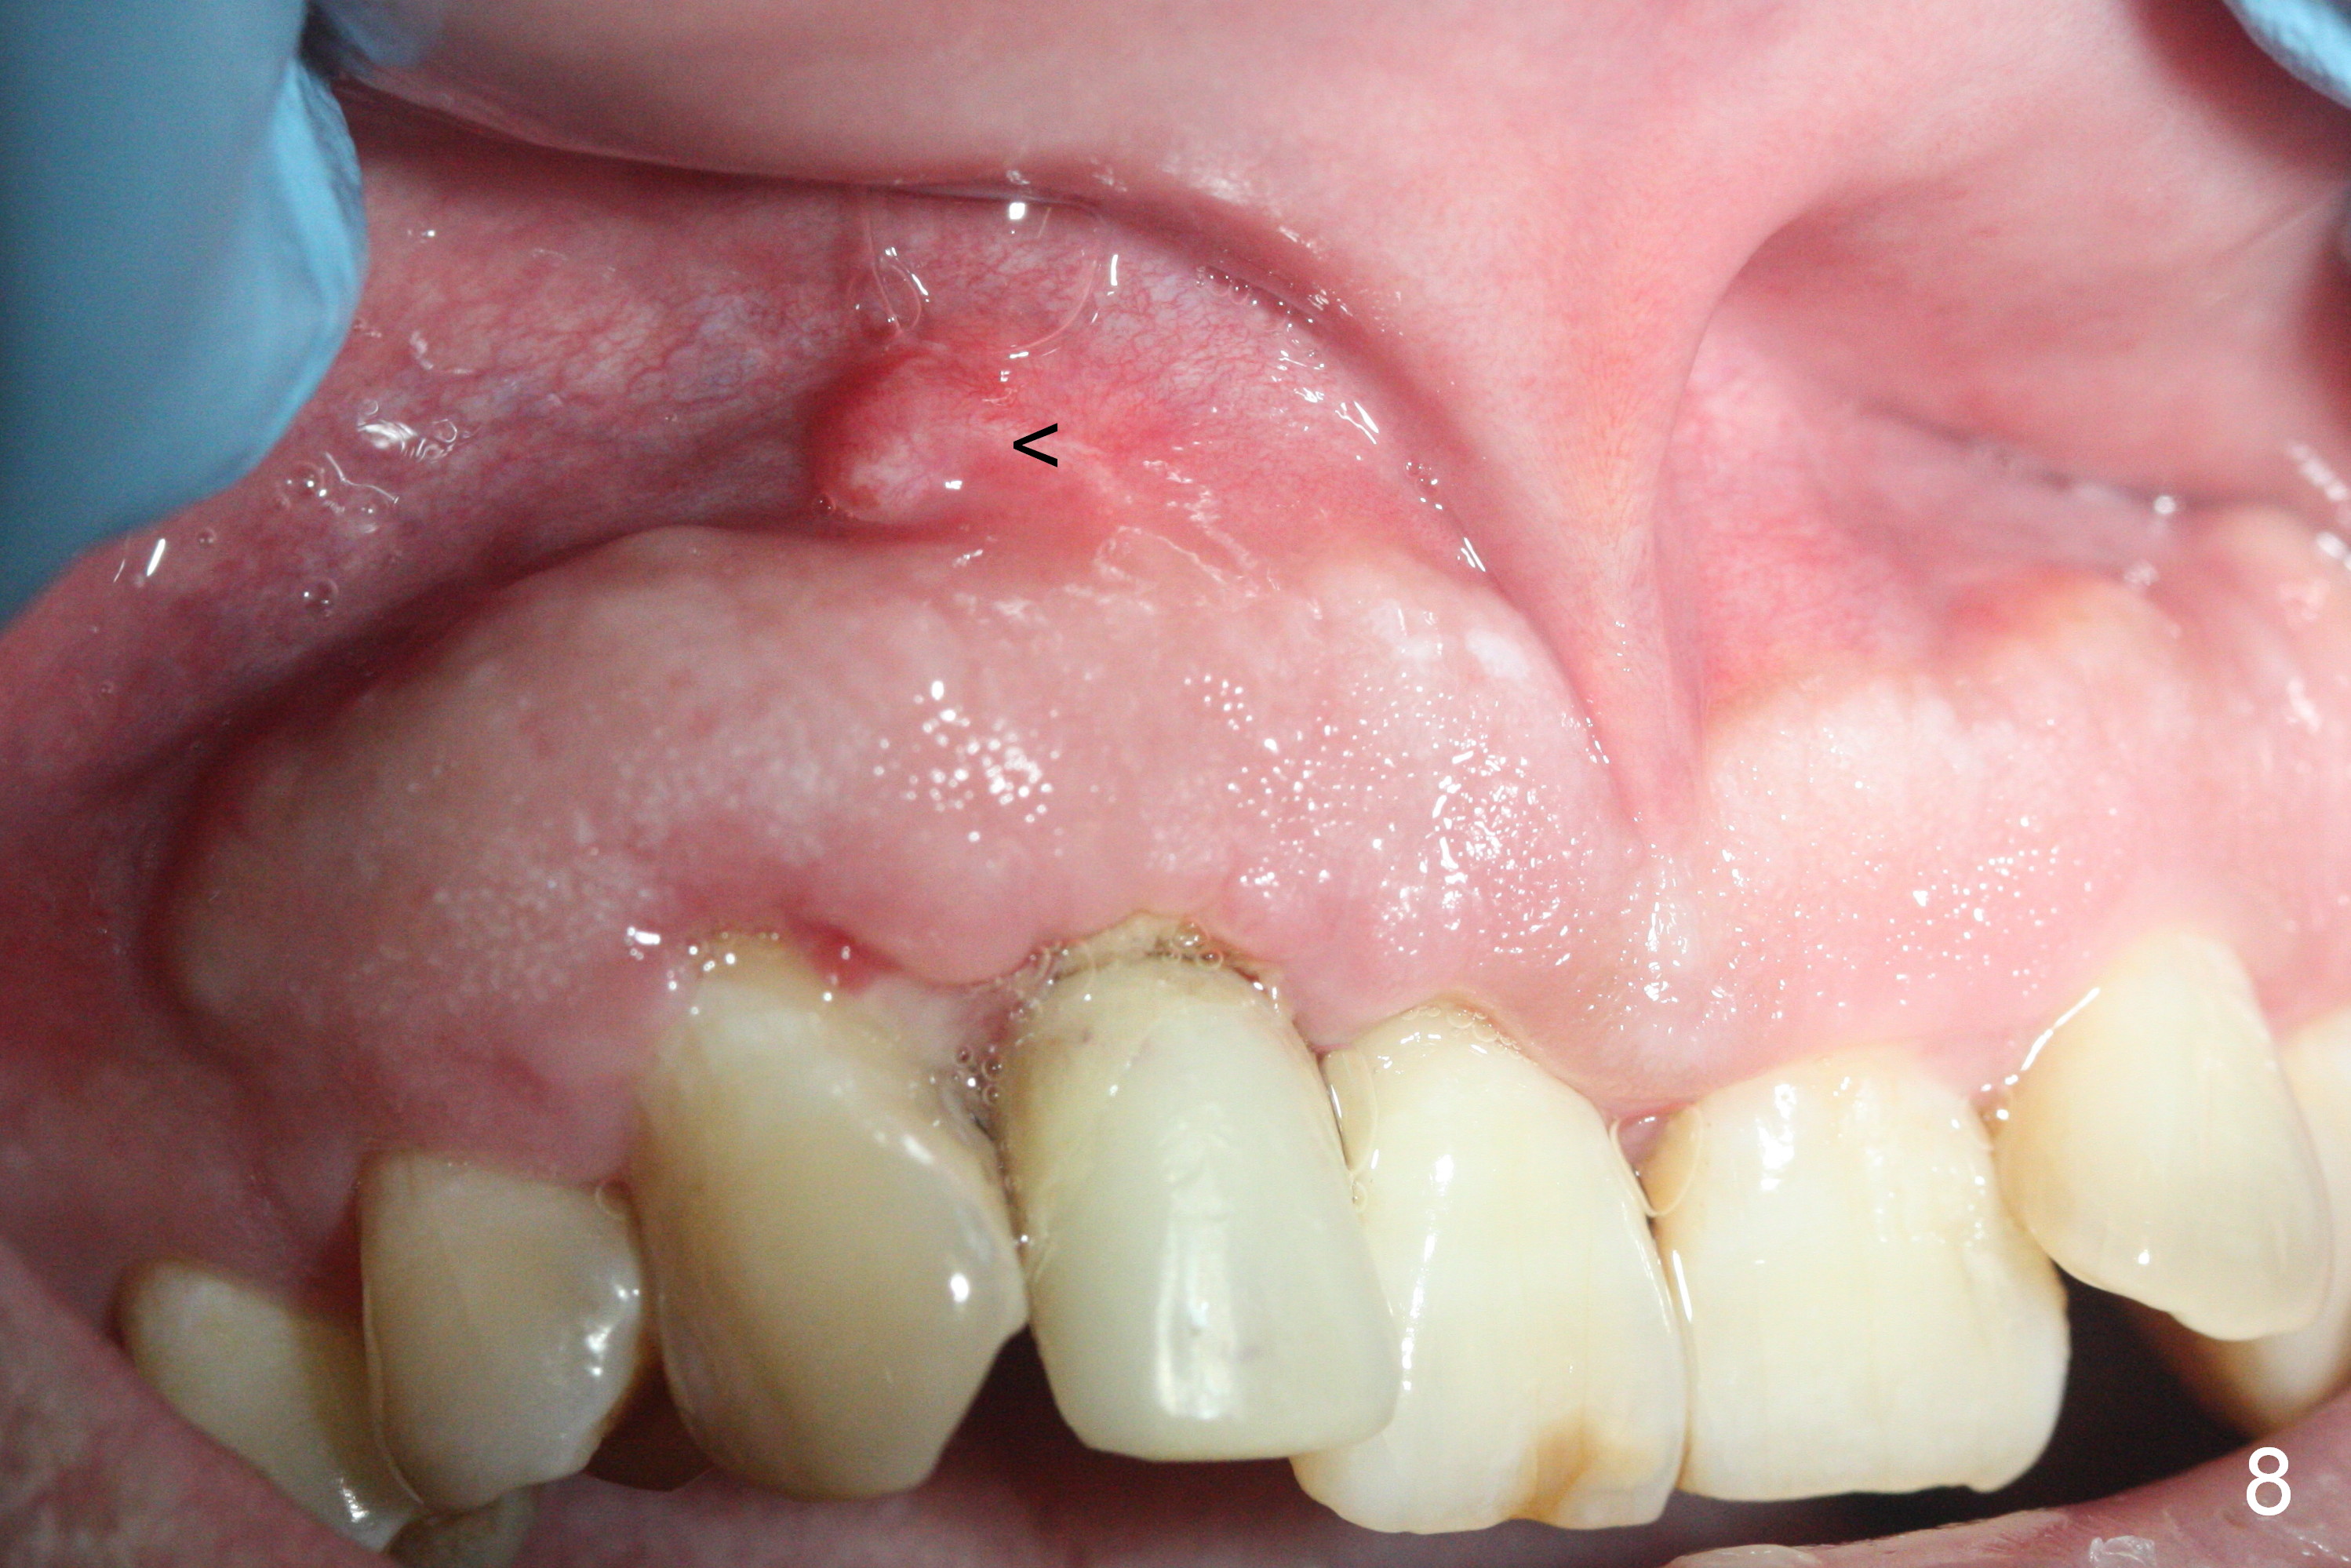

Sixteen days postop, the patient is doing fine, although the labial fistula has not disappeared (Fig.8 <). The detached distolabial papilla is healing (Fig.9 *) with mild bone graft exposure (^). The lacerated distopalatal papilla is also healing (Fig.10 *). These complications are related to flap surgery. The apical portion of the socket appears to have reduced 4 months postop (Fig.14). When the definitive restoration is delivered 5 months postop, there is gingival recession, including the distal of #8 (Fig.11 arrows, which is expected to improve over time) due to flap surgery. The labial plate collapse is minimal (Fig.12 *), while the palatal laceration (Fig.10) has healed (Fig.13). When the patient returns 1.5 years post cementation, there is increased bone density next to the coronal portion of the implant, equivalent to the bone graft (Fig.15 *). The fistula is absent (Fig.16). The crestal bone loss remains 2.5 years post cementation (Fig.17 *), although there is no sign of periimplantitis (magnification). Oral hygiene is poor. There is no change in the soft (gingival recession; data not shown) or hard tissues 3 years 8 months post cementation (Fig.18).